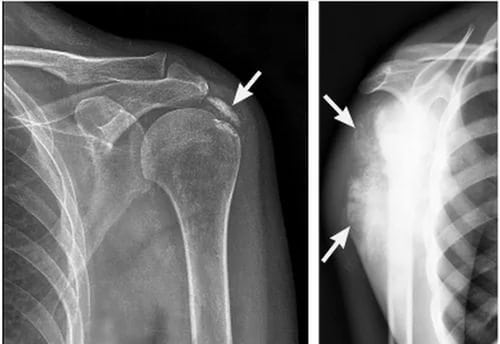

Наиболее информативно рентгенологическое исследование в диагностике патологии, МРТ, УЗИ, КТ. По полученным изображениям можно судить о локализации воспалительного процесса, стадии его течения, распространении на другие соединительнотканные структуры. Нередко на снимках обнаруживается вращающаяся шпора внизу акромиона.